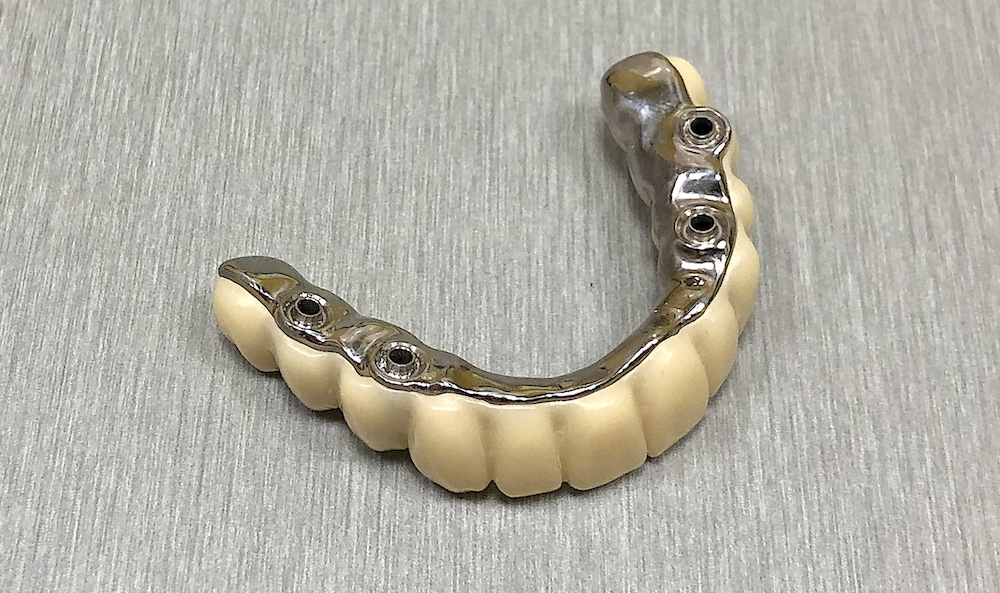

V posledních letech vidíme velký nárůst implantologických prací. Zhotovujeme náhrady na téměř 40 různých implantologických systémů, z nichž každý má několik variant podle typu, velikosti nebo řady implantátů. Každý implantát je jinak zavedený, a tak musíme vždy pečlivě rozhodnout, jaký cut použijeme podle toho jak hluboko je implantát zaveden.

Vnímáme také změnu preferencí lékařů – šroubované fixace jsou stále oblíbenější, ale někteří lékaři stále ještě dávají přednost cementovaným náhradám. Často také řešíme implantáty s odlišným sklonem, kde musíme rozhodnout, zda je nutné použít multiunit abutment.

Tohle všechno dělá práci s implantáty velmi komplexní. Není to jen o technice, ale hlavně o zkušenostech a schopnosti správně vyhodnotit každý případ.

3. Odevzdání hotové zubní náhrady.

Po odsouhlasení přesného dosedu, správného tvaru a skusu zhotovujeme definitivní zubní náhradu 👇